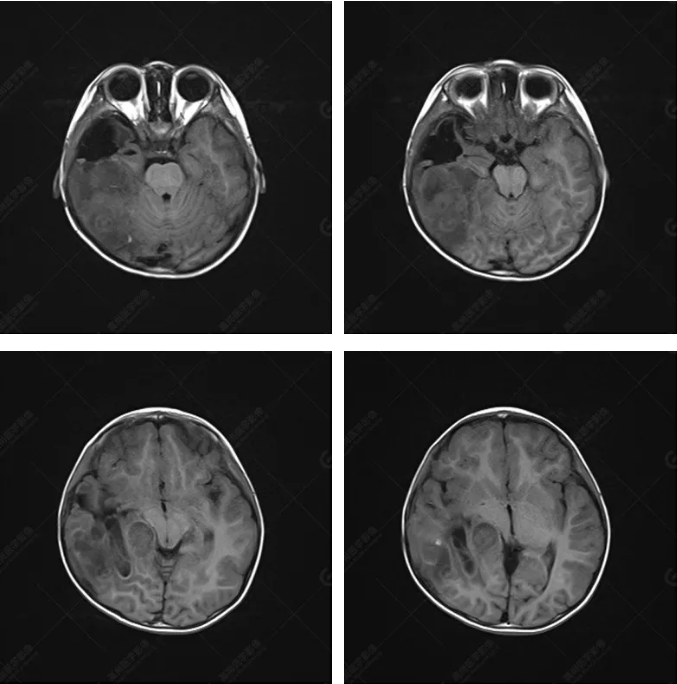

右側(cè)顳葉腫瘤切除術(shù)后(具體不詳):右側(cè)顳部骨質(zhì)不連續(xù)呈術(shù)后改變,右側(cè)顳葉術(shù)區(qū)見(jiàn)片狀長(zhǎng)T1長(zhǎng)T2信號(hào)影,F(xiàn)LAIR呈低信號(hào);術(shù)區(qū)后方右側(cè)顳枕葉見(jiàn)一巨大占位性病變影,邊界欠清,大小約6.2×5.8×4.3cm(前后×左右×上下),信號(hào)不均勻,T1WI呈等稍低信號(hào)間雜少許高信號(hào),T2WI呈高稍低混雜信號(hào),DWI示部分病灶彌散受限,相應(yīng)ADC圖減低,磁敏感序列見(jiàn)部分呈極低信號(hào),增強(qiáng)掃描可見(jiàn)明顯不均勻強(qiáng)化,鄰近硬腦膜及小腦幕增厚并明顯強(qiáng)化;另延髓右前方及右側(cè)橋小腦角區(qū)見(jiàn)一不規(guī)則形異常信號(hào)影,大小約3.2×1.3×3.7cm(左右×前后×上下),呈長(zhǎng)T1稍長(zhǎng)T2信號(hào),F(xiàn)LAIR呈等信號(hào),DWI未見(jiàn)受限,增強(qiáng)后明顯均勻強(qiáng)化,鄰近腦膜明顯強(qiáng)化。鄰近腦實(shí)質(zhì)及右側(cè)顳角明顯受壓;左側(cè)大腦半球未見(jiàn)局灶性信號(hào)異常,中線結(jié)構(gòu)稍左移。

右側(cè)顳葉腫瘤切除術(shù)后:現(xiàn)術(shù)區(qū)后方右側(cè)顳枕葉及延髓右前方占位,右側(cè)顳枕部硬腦膜及小腦幕明顯強(qiáng)化,結(jié)合既往影像資料,考慮為胚胎源性惡性腫瘤,如非典型畸胎樣/橫紋肌樣瘤(AT/RT)或原始神經(jīng)外胚層腫瘤(PNET)。

非典型畸胎樣/橫紋肌樣瘤(AT/RT) 是一種高度惡性中樞神經(jīng)系統(tǒng)腫瘤,臨床罕見(jiàn),臨床表現(xiàn)無(wú)特異性,好發(fā)于 5 歲以下兒童,尤以 3 歲以下多見(jiàn),在兒童原發(fā)性中樞神經(jīng)系統(tǒng)(CNS)腫瘤中占 1%~3%。該腫瘤體積一般較大,幕上大于幕下,有明顯的占位效應(yīng)。該腫瘤成分復(fù)雜,囊變、出血、壞死常見(jiàn)。因此 AT/RT信號(hào)混雜,囊性部分呈 T1WI低、T2WI高信號(hào),增強(qiáng)后不強(qiáng)化;若瘤體出血,囊內(nèi)可見(jiàn)T1WI稍高信號(hào)、T2WI低信號(hào),實(shí)性部分在 T1WI上呈混雜等、低信號(hào),在T2WI 及 T2-FLAIR上呈混雜等高信號(hào),增強(qiáng)掃描后大部分呈環(huán)形條帶樣明顯強(qiáng)化,中心壞死區(qū)不強(qiáng)化。另外,該腫瘤實(shí)性成分在DWI上呈高信號(hào),說(shuō)明腫瘤細(xì)胞核密集,水分子擴(kuò)散明顯受限,提示該腫瘤惡性程度高,容易復(fù)發(fā)及轉(zhuǎn)移。